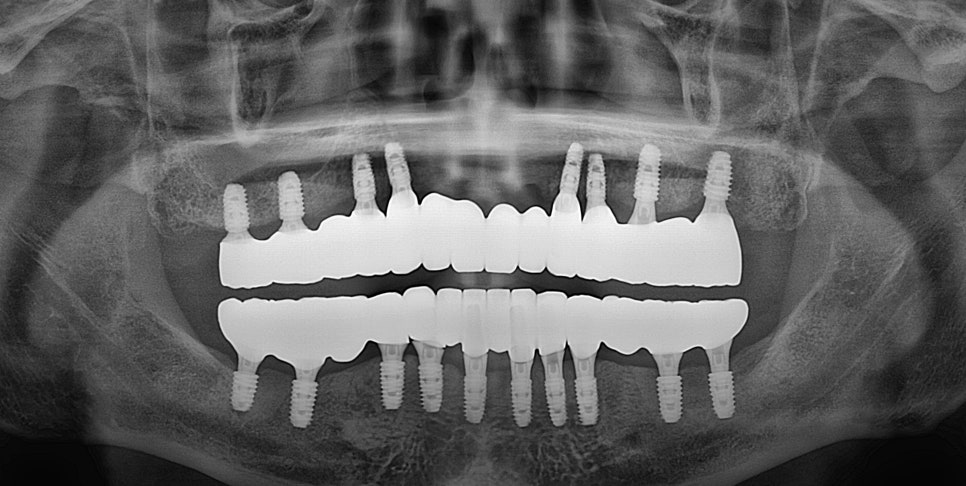

이후 최종 보철이 장착된

사진입니다.

당일 기공 작업을 끝내

즉시 하중을 부하했습니다.

그렇기에 전체 임플란트

기간을 단축시킬 수 있었죠.

2024.12.11